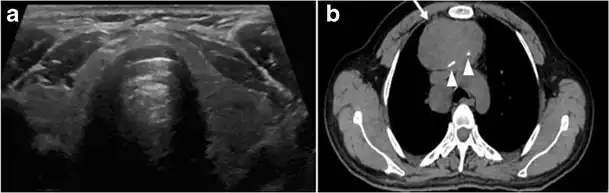

Fig. 14. A 19-year-old male patient known to have multi-nodular goiter and FNA, showing underlying Hashimoto's thyroiditis. a, b Sagittal and transverse greyscale and colour Doppler ultrasound of the neck demonstrate a hypoechoic enlarged right thyroid lobe with small hyperechoic regenerative nodules and marked hypervascularity (white arrows). c, d Enhanced axial CT scan images of the neck demonstrate a heterogeneously enhancing and enlarged thyroid gland, left more than right lobe, and the trachea is markedly narrowed.[1]

Fig. 15. A 33-year-old female patient who presented with neck swelling and pain and was later diagnosed with Hashimoto's thyroiditis. an Axial enhanced CT scan of the neck demonstrates minimal diffuse enlargement of the thyroid gland, especially the isthmus (white arrow). b Transverse greyscale ultrasound of the neck demonstrates heterogeneously enlarged thyroid and thickened isthmus, measuring 8.6 mm.[1]